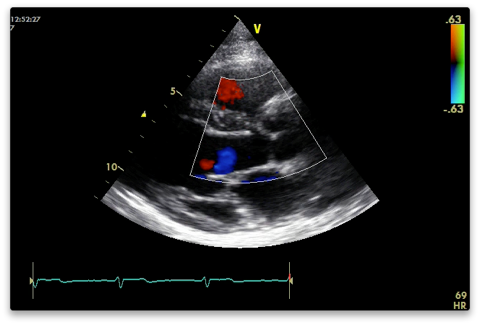

Colour (Nyquist limit 50-60 cm/s)

Aortic and mitral valves for stenosis and regurg. Do one at a time. The resolution is better the narrower and shallower you have the colour box (cutting off the near field makes no difference).

Measure vena contracta if present (narrowest width of regurg colour).

Colour M-mode for AR if present - measure jet width and calculate as percentage of LVOT width.

LVOT for flow acceleration if septal hypertrophy